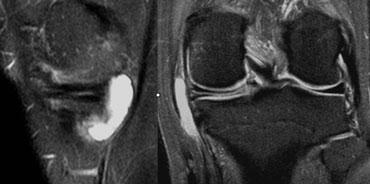

Ảnh PD và T2W. Tiền sử cắt sụn chêm một phần và khâu phục hồi. Khi nội soi khớp, không phát hiện rách.

Sụn chêm sau phẫu thuật 1

Trường hợp bên trái cho thấy sụn chêm có hình dạng bất thường cũng như tín hiệu bất thường chạm đến bề mặt trên ảnh PD nhưng không thấy trên ảnh T2W.

Bệnh nhân này có tiền sử cắt sụn chêm một phần và khâu phục hồi.

Dựa trên các phát hiện hình ảnh này, không thể xác định đây là rách hay là hình ảnh bình thường sau phẫu thuật.

Bệnh nhân này được phẫu thuật lại để tái tạo dây chằng chéo trước (ACL).

Phẫu thuật viên đã quan sát sụn chêm và xác nhận sụn chêm bình thường, tức là không có rách.